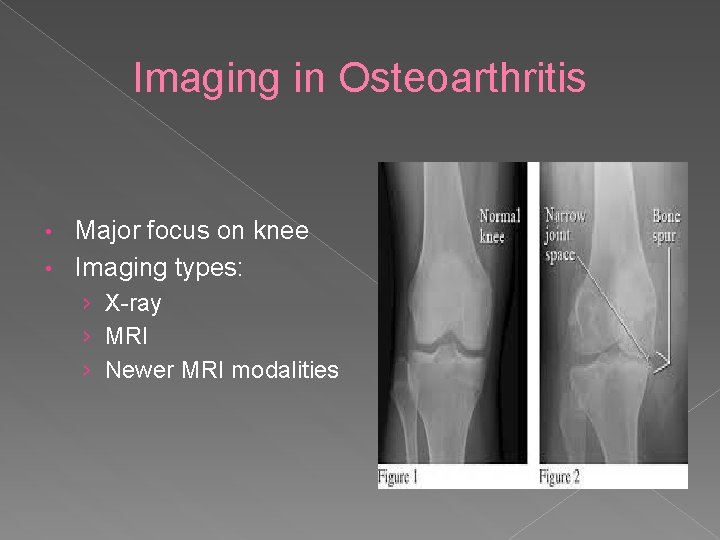

Imaging in Osteoarthritis Major focus on knee • Imaging types: • › X-ray › MRI › Newer MRI modalities

X-ray Simplest imaging technique • First Line • Can detect OA-associated bony features: • › › • Marginal osteophytes Subchondral sclerosis Subchondral cysts. Joint space width (JSW) - an indirect surrogate of cartilage thickness and meniscal integrity. Joint space narrowing (JSN) is the key end point currently for interventional studies

X-ray Findings • • • Non-uniform narrowing of joint space Subchondral bony sclerosis Marginal osteophyte formation Subchondral Cyst formation Gross deformity in advanced cases

Joint Space Narrowing